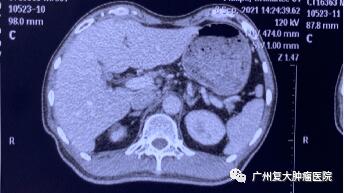

为求进一步诊疗,2020年11月,患者来广州复大肿瘤医院就诊。入院完善相关检查发现:CA-199指标高达2289u/ml(CA-199属胃肠道肿瘤相关抗原,是一种肿瘤标志物,正常值≤37u/ml);肝实质内有多个结节状,较大者约4.3×3.8cm。胰腺体、尾部均有肿块,并邻近肠管、脾静脉局部粘连不清,大小约4.3x3.3cm。

影像图片显示

图3